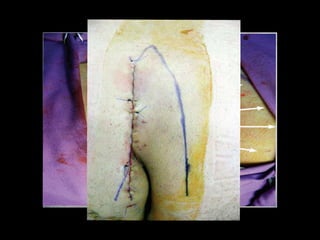

K A R Y D A K I S A N D B A S S C O M ’ S

• Technique for excision

• Karydakis excised up to the sacrum, modified by Bascom.

• Karydakis had less than 1% recurrence with this

procedure

• Mean hospital stay is .76 days, Healing 11.1 days, Return

to work in 17.7 day

Karydakis Flap